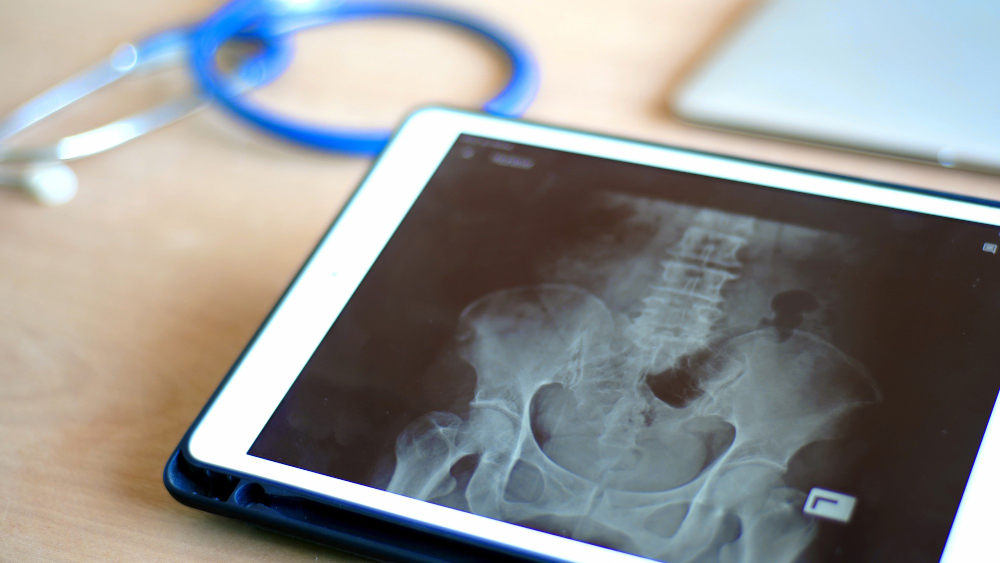

• X-ray: For older babies and children, X-rays show the bones more clearly.